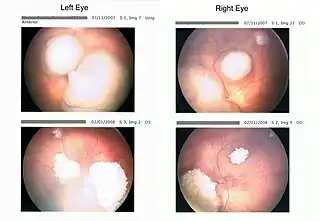

Tumores del retinoblastoma tomados con un "retinoscan" antes y durante la quimioterapia. | ||